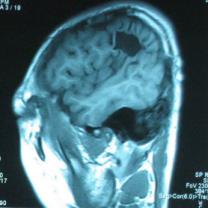

頭顱CT和MRI可見顱骨缺損區(qū)下方軟腦膜囊腫、腦軟化灶或腦室穿通畸形(圖2)。

圖2:①和②CT及骨窗相顯示右頂部顱骨缺損,其下方腦組織呈低密度改變;③-⑥MRI右頂局部顱骨缺如,腦組織輕度向外膨隆,右頂葉側(cè)腦室體部旁局部腦組織缺如,代之以囊性長T1、長T2信號。